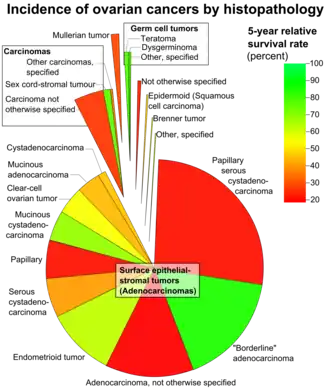

Papillary serous cystadenocarcinomas are the most common form of malignant ovarian cancer making up 26 percent of ovarian tumours in women aged over 20 in the United States.[1]